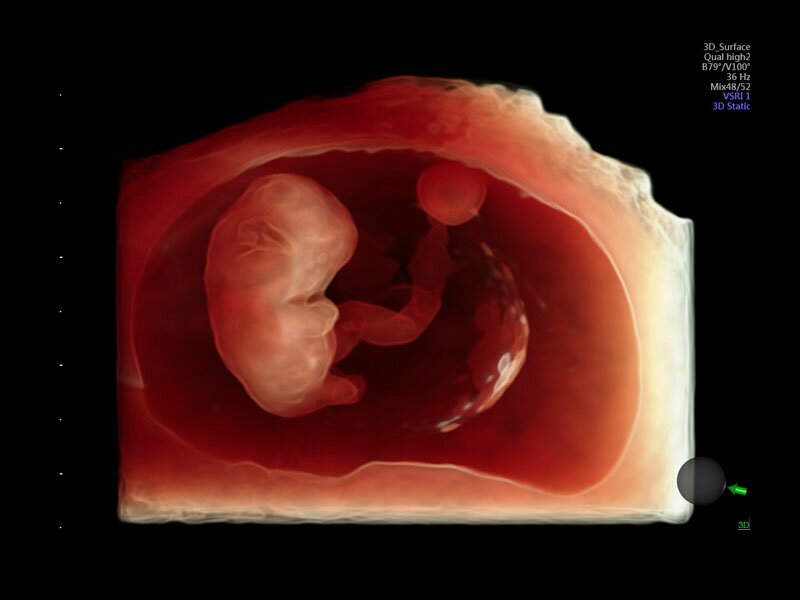

• Программа объемной визуализации плода классический HD-Live + расширенный пакет Hdlive Silhouette и Studio:

• HDlive Silhouette - режим "Силуэт" с подчеркиванием границ тканей и объектов, "объем в объеме"

Современные клинические приложения и высокое качество изображений позволяют использовать Voluson E10 для наблюдения за ходом беременности максимально эффективно. С помощью этого аппарата можно проводить любые исследования, как рутинные, так и комплексные, выявляя проблемы на ранних стадиях и принимая своевременные меры.

Объемное УЗИ на Voluson E10 — это не просто потрясающе красивая картинка, это ценный инструмент получения дополнительной информации при обследовании женщин.

Voluson E10 поддерживает инновационные технологии формирования изображений — HDlive Silhouette и HDlive Flow, которые позволяют увидеть мельчайшие детали. Алгоритм SonoRenderlive упрощает рабочий процесс и дает возможность реконструировать изображение поверхностей, определяя область перехода между тканью и жидкостью.

• Технология HDlive Silhouette — задает разный уровень прозрачности, помогая выявлять контуры внутренних структур и точнее оценивать состояние плода в первом триместре.